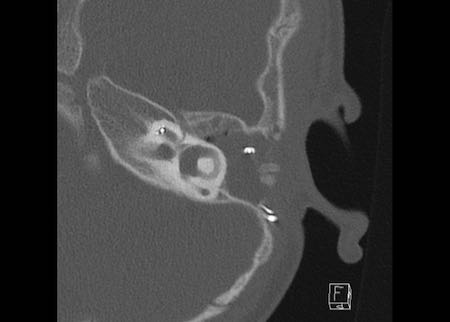

Bên trái là hình ảnh của một bé gái 2 tuổi.

Các hình ảnh từ kết quả chụp CT được thực hiện trước khi cấy ốc tai điện tử.

Quan sát thấy dị dạng nhẹ ở đỉnh ốc tai – không có sự phân tách giữa vòng thứ hai và vòng thứ ba, và trụ ốc tai xương vắng mặt.

Cống tiền đình bình thường.